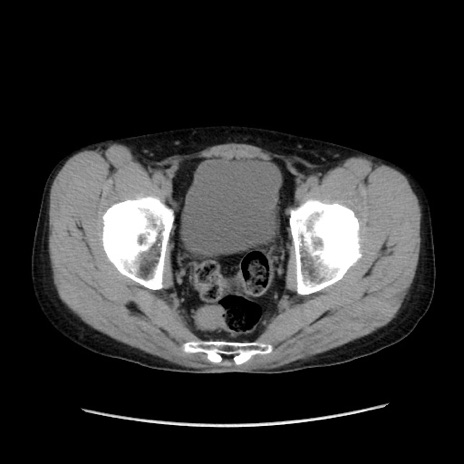

冠状断像